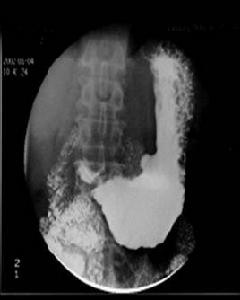

龕影:胃腸道壁上的潰瘍或凹陷達到一定深度後,能被鋇劑充填,在切線位投射時,就形成一個突出的影像稱為壁龕或龕影。

龕影(niche)是指鋇劑塗布的管腔輪廓有局限性外突的影像,為消化性潰瘍及腫瘤壞死性潰瘍形成的腔壁凹陷,使鋇劑充填滯留其內所致。軸位觀潰瘍呈火山口狀。 龕影(crater)是由充鋇的胃腸輪廓某局部向外凸出的含鋇影像。來自胃腸道壁的局限性缺損,見於胃腸道潰瘍,也是作為描述潰瘍的鋇劑造影表現。

龕影壁光滑,位於胃腔輪廓之外常提示良性病變,如胃潰瘍;可以有黏膜線、項圈征和狹頸征,可見黏膜放射狀糾集,為修復表現。

龕影邊緣不整,位於胃腔輪廓之內常提示惡性病變,如胃癌; 可見指套征、局部黏膜中斷、破壞,胃壁僵硬,蠕動消失。